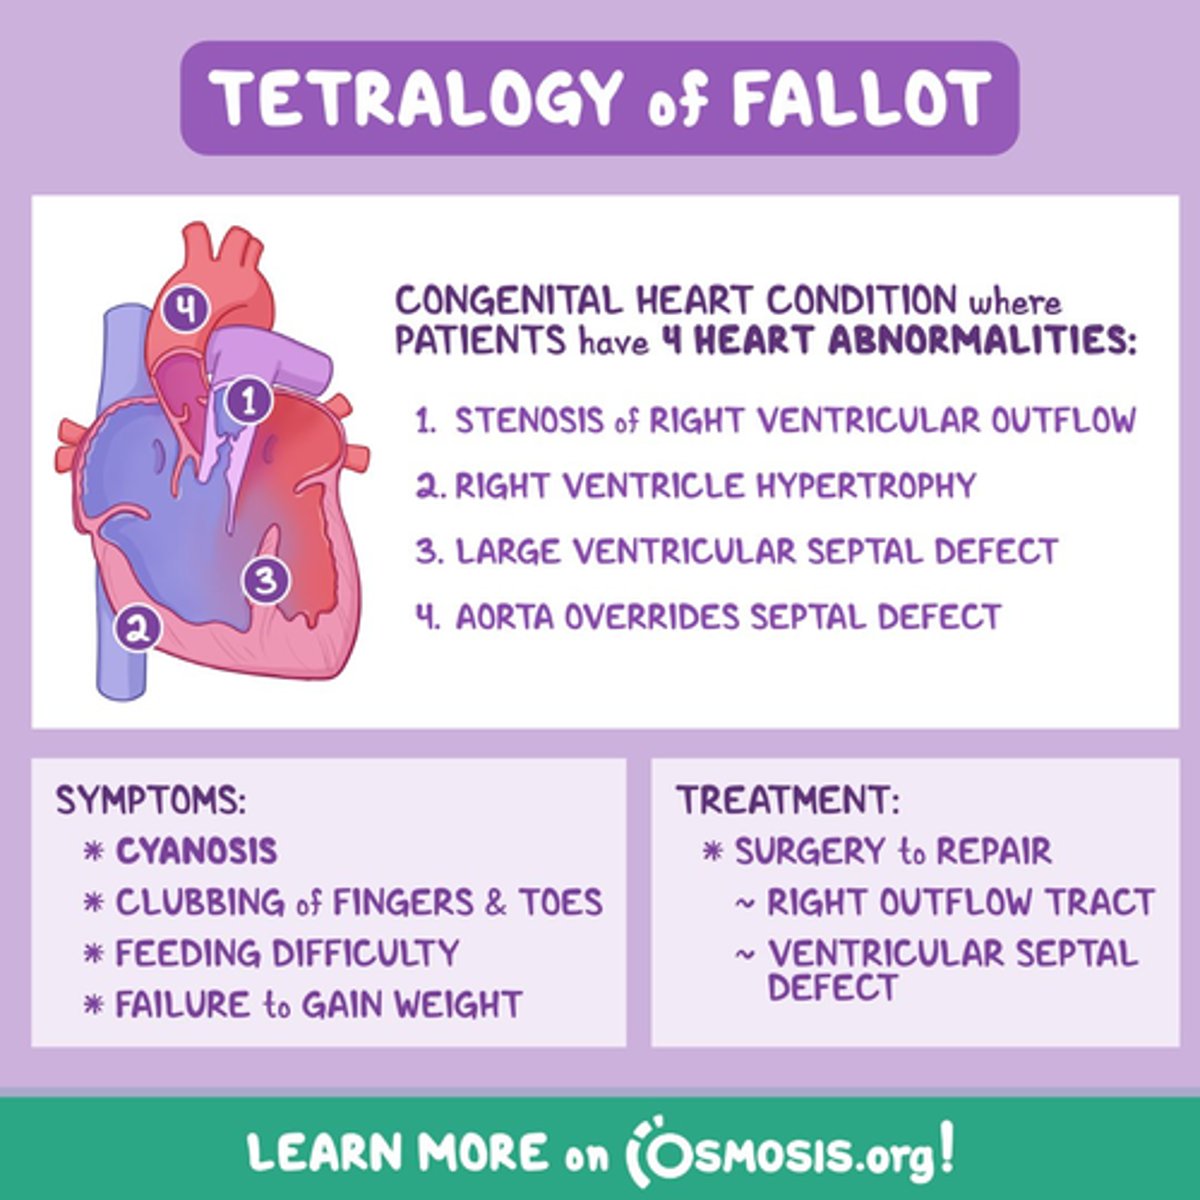

What is the MC cyanotic CHD?

Tetralogy of Fallot - boot shaped heart

PS

RVH

Overide aorta

VSD